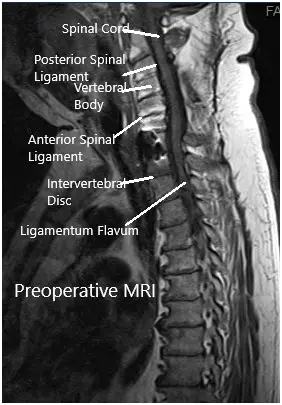

Imaging study revealed lateral disc herniations encroaching upon the neural foramen at C7-Tl and at Tl-T2, causing critical stenosis. Given his constellation of systems and weakness, we suspected also that he had a postfixed brachial plexus. obtained a thorough workup given the complexity of the patient’s imaging findings and clinical presentation and included MRI of the brain and brachial plexus.

MRI suggested postoperative changes with the fusion of the facets from C3-C7 bilaterally with laminectomies. C7-T1 vertebral bodies are fused anteriorly. There is a resultant artifact as the result of the hardware.

Mild signal abnormality in the spinal cord at C5-6 of uncertain chronicity. At T1-T2 broad-based disc bulge with articular recess narrowing bilaterally. There were lateral disc herniations encroaching upon the neural foramen at C7-Tl and at Tl-T2, causing critical stenosis.

Preoperative MRI in the sagittal section.